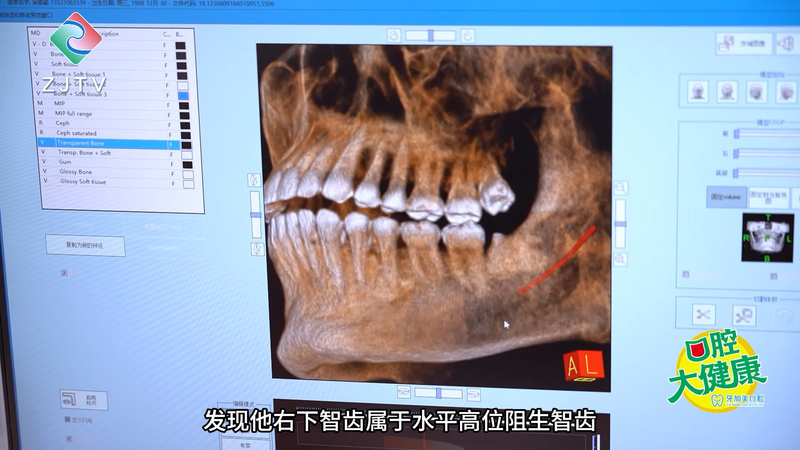

陈先生来到湛江牙加美口腔,经过医生面诊和口腔影像诊断,发现他右下智齿属于水平高位阻生智齿。

苏东明医生:从片子可以看出,患者右下智齿是横着长的,这类智齿不仅容易留存食物引发炎症,还可能导致邻牙疼痛甚至龋坏,所以阻生智齿一般都是建议拔除的。